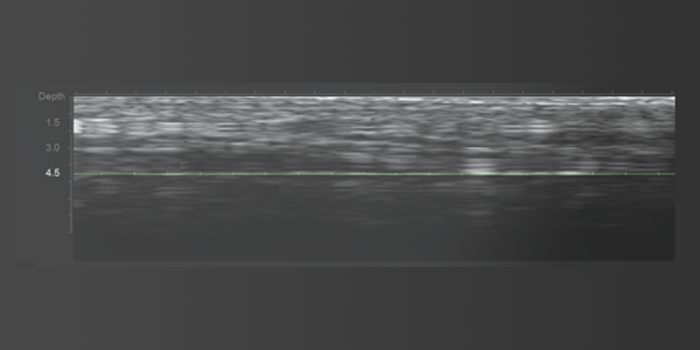

Real-time skin layer monitoring up to a maximum depth of 8mm,Customized treatment

ensuring a safer and more precise treatment without nerve damage.

Safe Treatment

Real-time skin layer monitoring reduces the likelihood of side effects such as nerve damage and cheek indentation.

Accurate Targeting

Precise energy delivery to the targeted area with accurate location selection.

Effective

Effective energy reaches the correct skin layer, increasing the lifting effect.